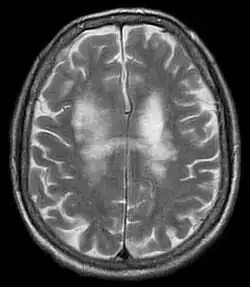

Progresivní multifokální leukoencefalopatie (PML), známá též jako progresivní multifokální leukoencefalitida, je vzácné a obvykle fatální virové onemocnění, které je charakteristické progresivním poškozením (-patie) nebo zánětem bílé hmoty (leuko-) mozku (-encefalo-) na různých místech (multifokální). Vyskytuje se téměř výhradně u lidí s těžkou imunodeficiencí, například u pacientů po transplantaci na imunosupresivech, u pacientů podstupujících některé druhy chemoterapie, lidí s roztroušenou sklerózou užívající natalizumab (Tysabri),[1] pacientů s psoriázou dlouhodobě užívající efalizumab (Raptiva)[2] či pacientů s AIDS.

Jejím původcem je JC virus. Diagnostikuje se pomocí počítačové tomografie (CT), magnetické rezonance (MRI), analýzou mozkomíšního moku získaného lumbální punkcí, či biopsií.[3]